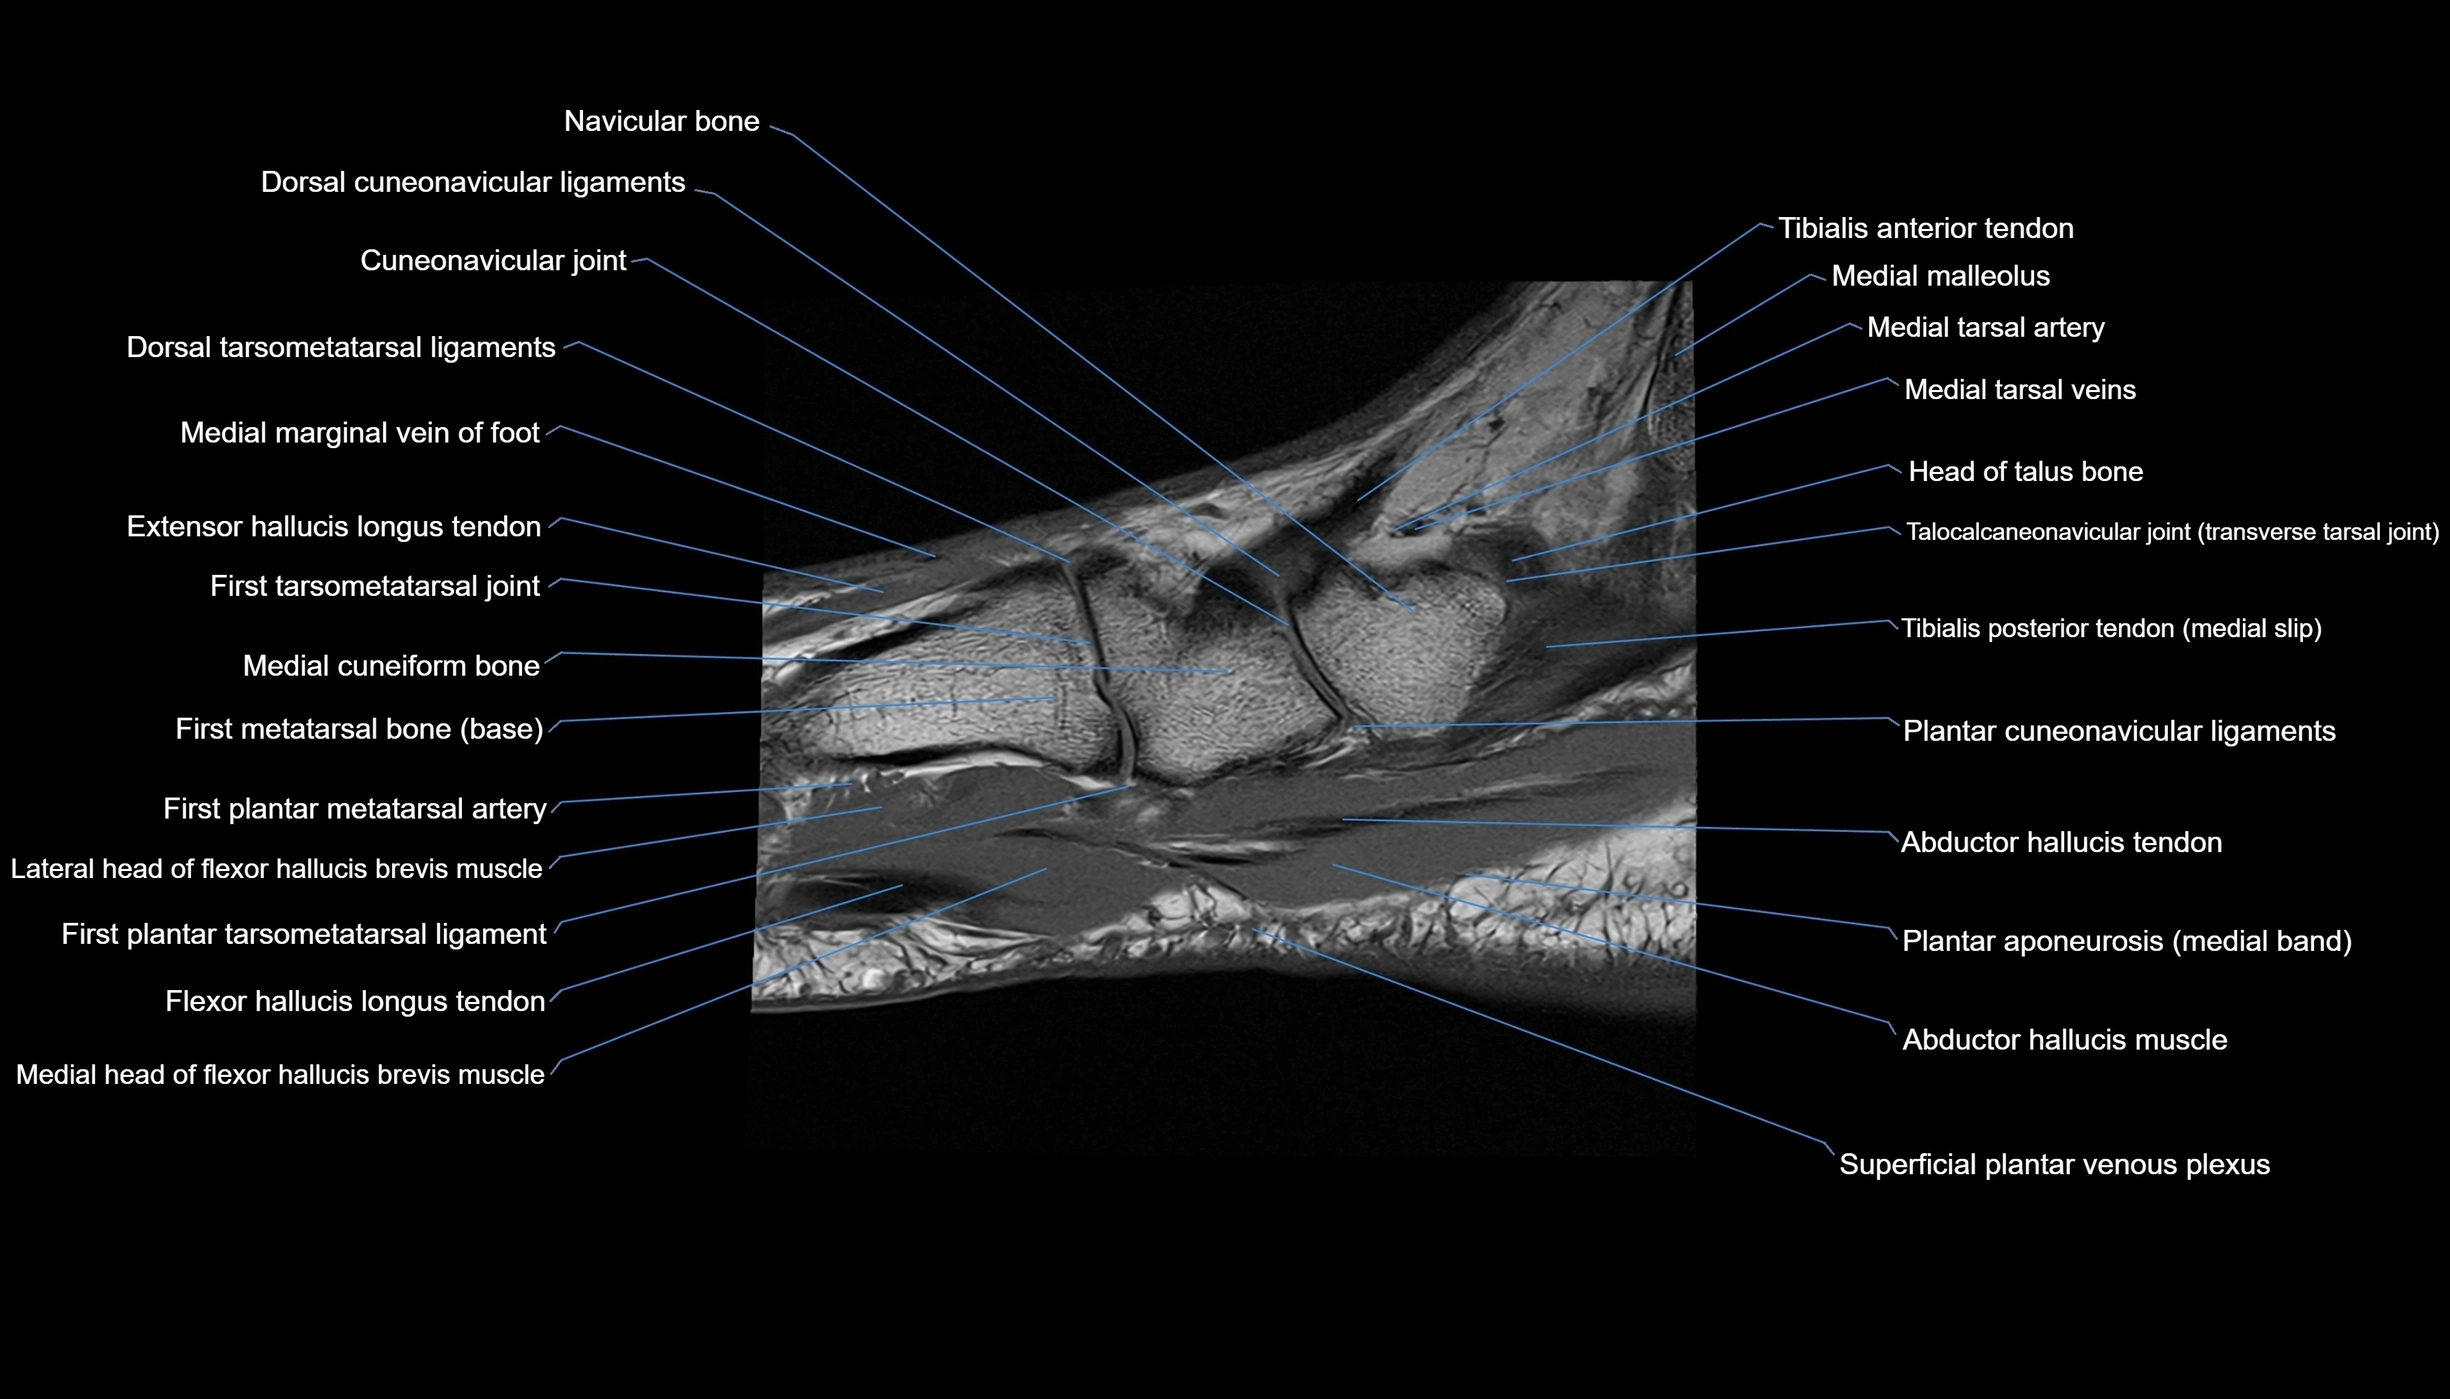

MRI image